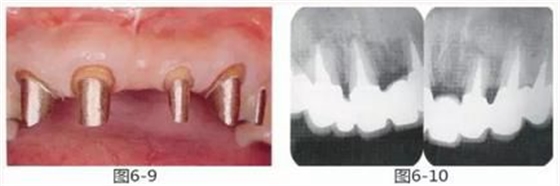

圖6-9 牙周外科治療5個(gè)月后,最終取模前的狀態(tài)?;乐車@得了充足的附著齦。

圖6-10 佩戴最終修復(fù)體時(shí)的X光照片。